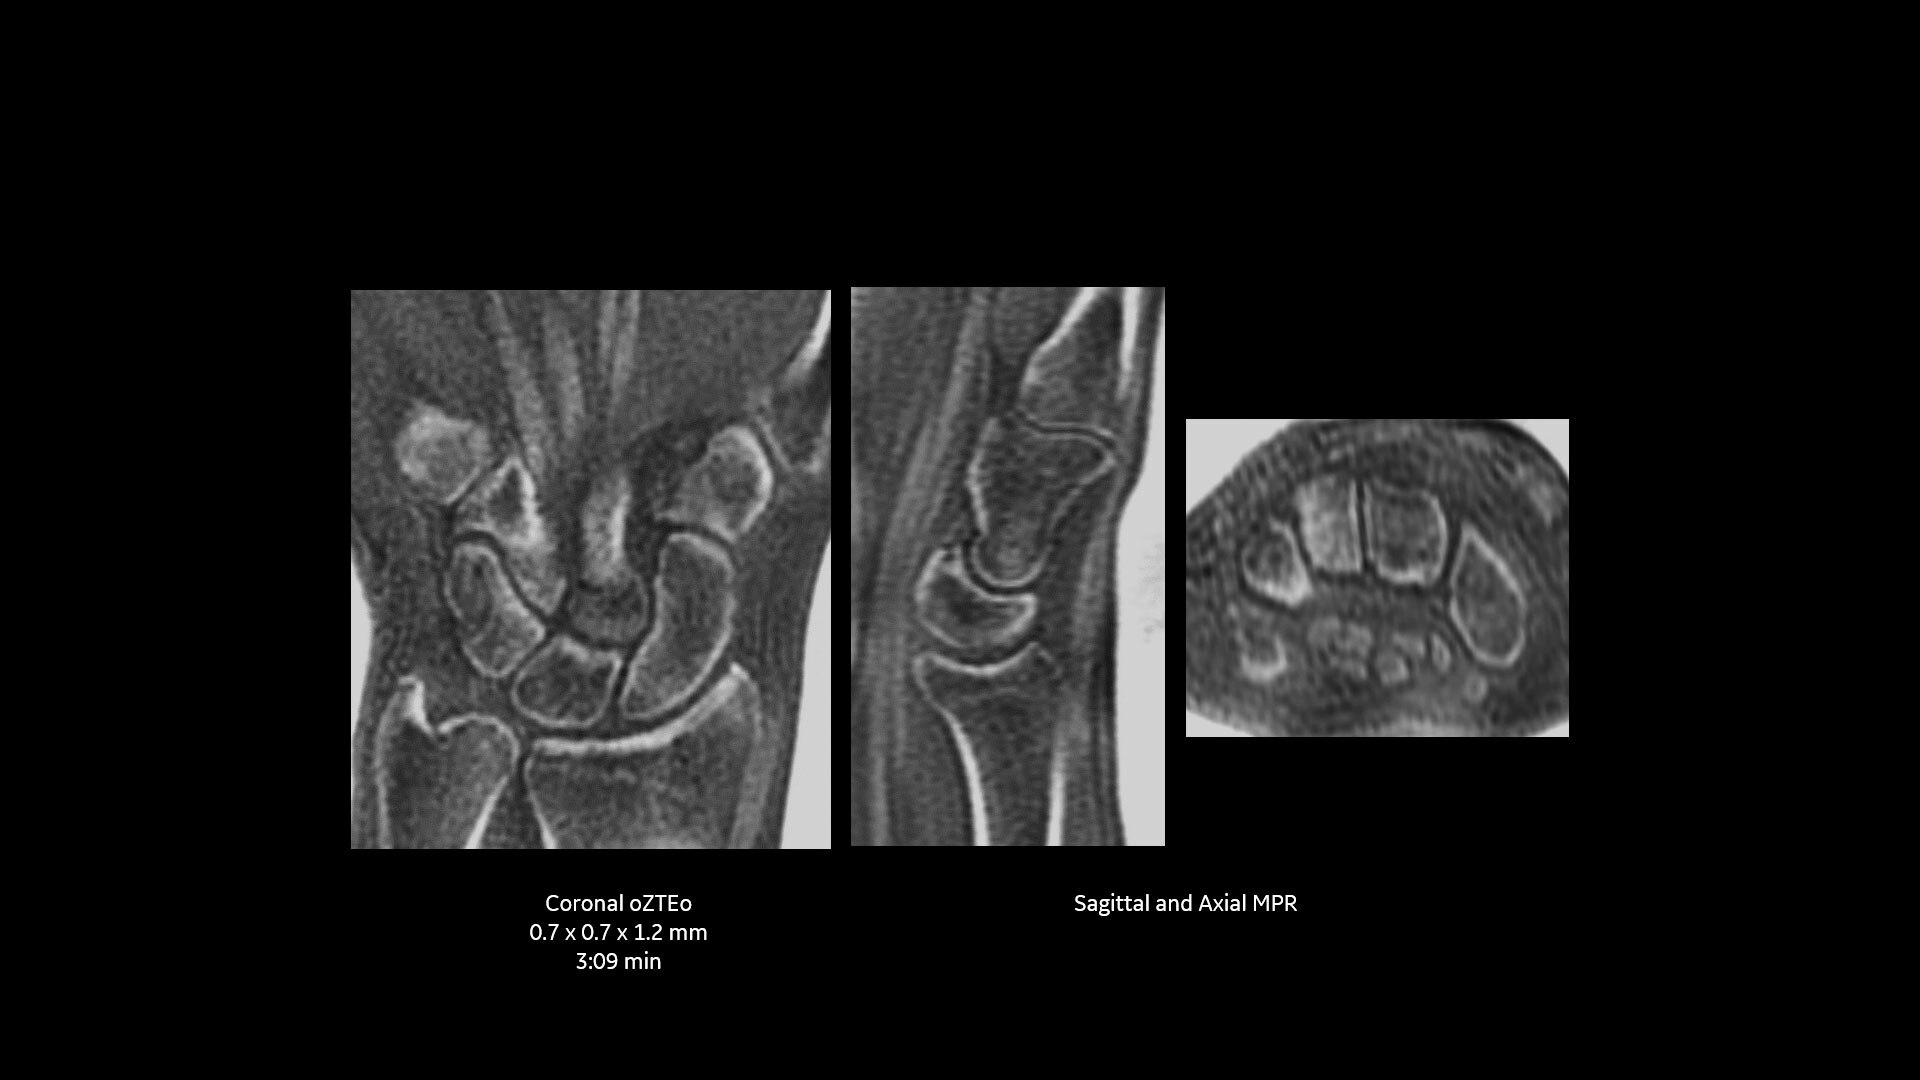

Powerful bone imaging for all anatomies

Available for all anatomies without ionizing radiation, oZTEo delivers images of bone morphology, calcification, ossification and fractures. oZTEo complements conventional MR soft tissue exams with perfect co-registration and provides 3D isotropic imaging using a radial ZTE acquisition, with inherent motion insensitivity. Use oZTEo with Volume Illumination for realistic 3D rendering.